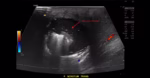

Diagnosis of Pneumoperitoneum Using POCUS

Maria Paulina Maya Jaramillo; Alejandro Cardozo Ocampo – This case report reinforces the value of integrating POCUS into the initial evaluation of acute abdominal pain, suggesting its use as an adjunct to traditional imaging methods in the emergency department.